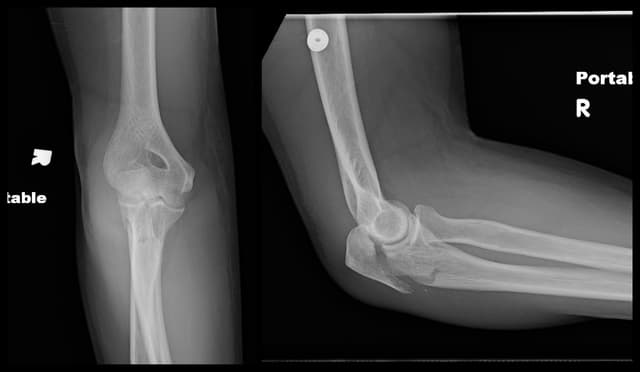

Imaging

Pre-op